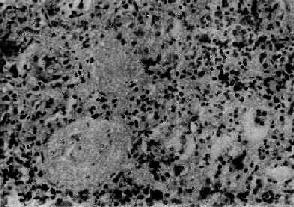

病变为弥漫性,两侧肾同时受累。病变进展较快,主要变化为肾小球内细胞增生。早期,肾小球毛细血管充血,内皮细胞和系膜细胞肿胀增生并有少量中性粒细胞浸润。毛细血管通透性增加,血浆蛋白质可以滤过而进入肾球囊。因此,病人的尿液中常有蛋白、红细胞及白细胞。轻型病人,病变可不再发展,以后逐渐痊愈;比较严重的病例,病变继续发展,肾小球内细胞增生加重。增生的细胞主要为系膜细胞和内皮细胞。增生细胞压迫毛细血管,使毛细血管腔狭窄甚至闭塞,肾小球呈缺血状(图12-7)。此外,肾小球内有多数炎性细胞浸润,主要为中性粒细胞,有时并有少数嗜酸性粒细胞、单核细胞、红细胞、浆液和纤维素性渗出液。镜下,肾小球内细胞数量增多,肾小球体积增大。病变严重时,毛细血管腔内可有血栓形成,毛细血管壁可发生纤维素样坏死。坏死的毛细血管袢破裂出血,大量红细胞进入肾球囊及肾小管腔内,可以引起明显的血尿。不同的病例病变表现形式可能不同。有的以渗出为主,称为急性渗出性肾小球肾炎。有些病变严重,肾小球毛细血管袢坏死,有大量出血者称为出血性肾小球肾炎。

图12-7 弥漫性毛细血管内增生性肾小球肾炎

肾小球内细胞数量增多,系膜细胞和内皮细胞增生并有少量中性白细胞浸润,毛血管腔狭窄